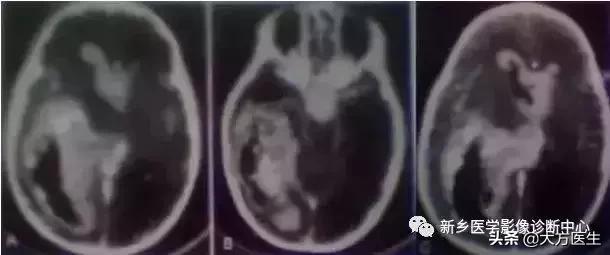

13、节细胞胶质瘤

节细胞瘤:钙化不到35%,特点是钙化常位于肿瘤囊变区。节细胞胶质瘤:钙化为囊周围壁钙化。

左为节细胞胶质瘤,右为节细胞瘤